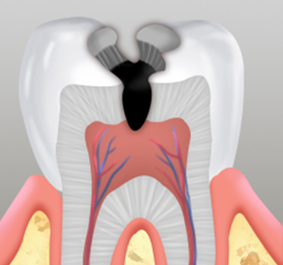

온도차 뿐 아니라

음식을 먹을 때 통증 발생

충치가 제거된 부위에 모양을 본 떠 금, 도자기 등의 재료로 구성된 보철물을 접착합니다.